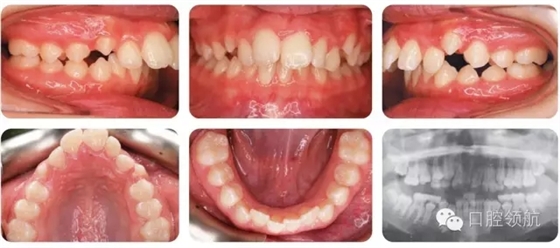

12歲的女性患者,由全科牙醫(yī)轉(zhuǎn)診。該患者健康情況良好,主訴是前牙前突(圖2.1)。

圖2.1

口內(nèi)相中的牙列處于哪一階段?

早期恒牙列。除LL7部分萌出以外,其余第二磨牙尚未萌出。

錯(cuò)牙合的主要特點(diǎn)有哪些?

● 安氏II類1分類,深覆蓋,深覆牙合,下前牙咬在上前牙腭側(cè)黏膜。

● 右側(cè)磨牙1/2牙尖Ⅱ類關(guān)系,左側(cè)磨牙I類關(guān)系。

● 中線一致。

● UL2多生牙已萌出。

雙側(cè)磨牙關(guān)系為何不一致?

左上牙列存在一顆多生牙,但中線基本一致,說明UL6比正常位置偏遠(yuǎn)中,所以更接近I類關(guān)系而不是II類。